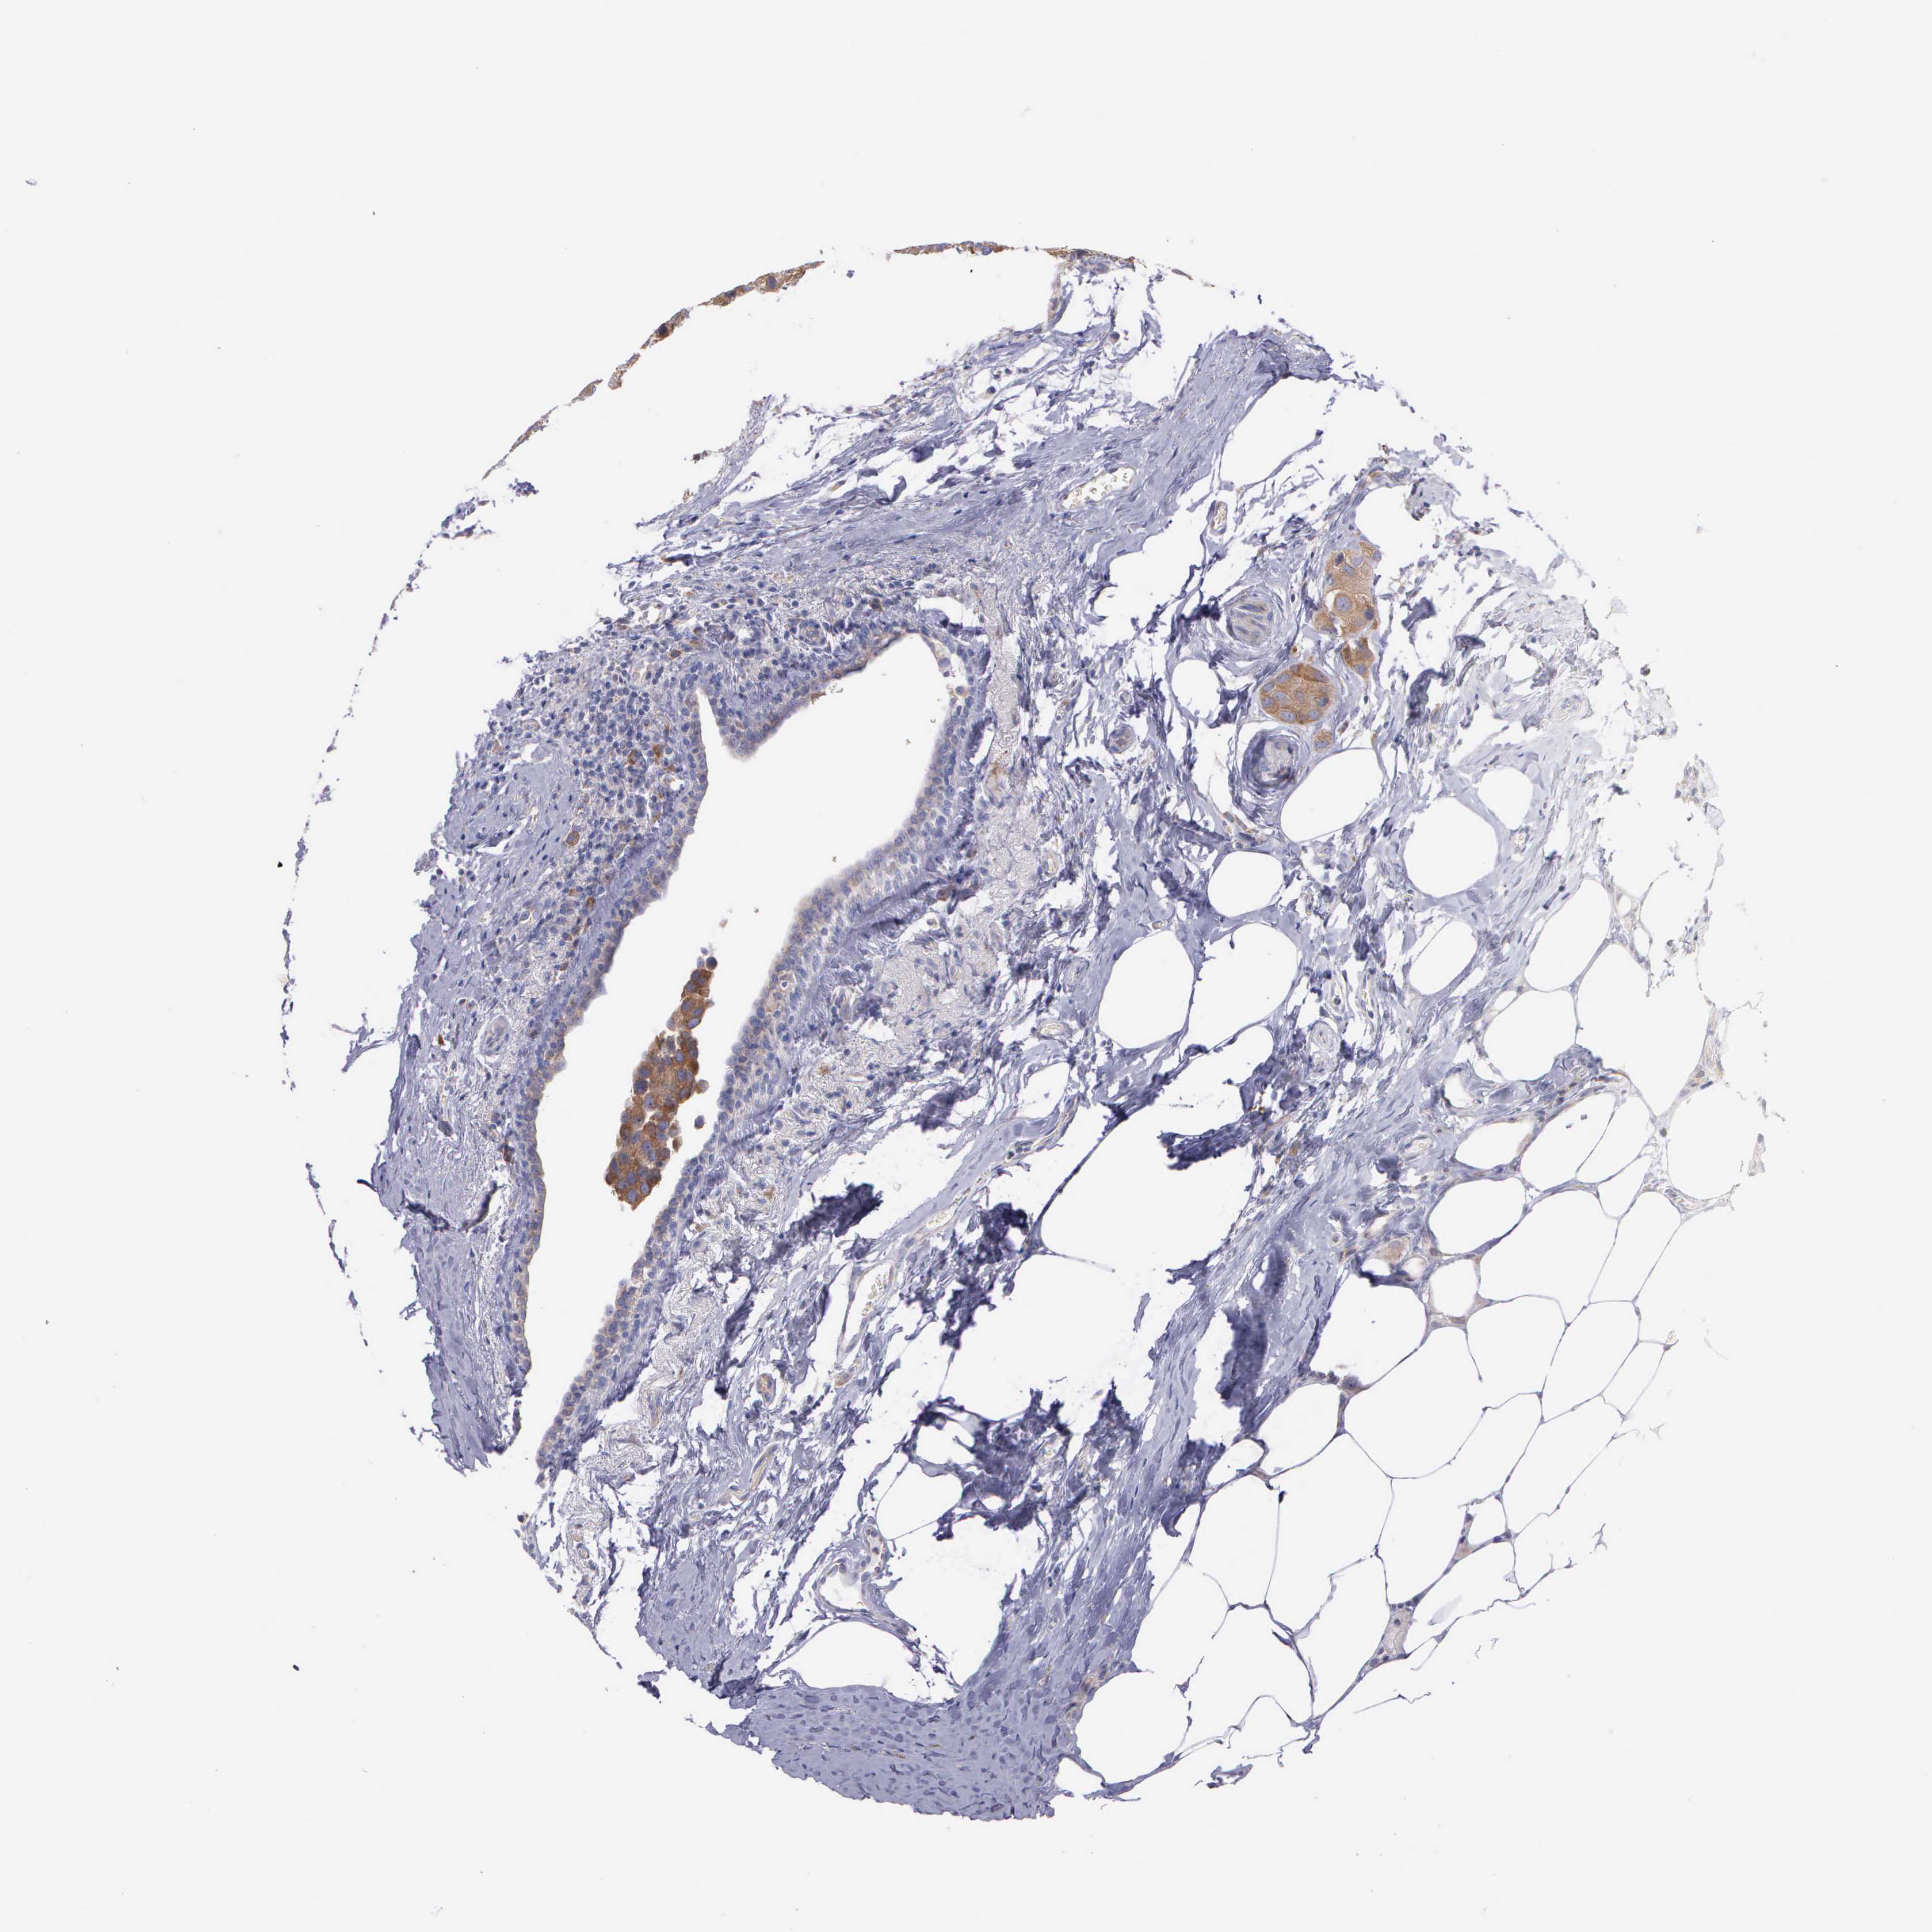

BREAST CANCER - Protein expressioni

A mouse-over function shows sample information and annotation data. Click on an image to view it in a full screen mode. Samples can be filtered based on level of antibody staining by selecting one or several of the following categories: high, medium, low and not detected. The assay and annotation is described here.

Note that samples used for immunohistochemistry by the Human Protein Atlas do not correspond to samples in the TCGA dataset.

Antibody stainingi

Antibody staining in the annotated cell types in the current human tissue is reported as not detected, low, medium, or high, based on conventional immunohistochemistry profiling in selected tissues. This score is based on the combination of the staining intensity and fraction of stained cells.

Each image is clickable and will lead to virtual microscopy that enables deeper exploration of all samples and also displays staining intensity scores, fraction scores and subcellular localization as well as patient and tissue information for each sample.

Antibody HPA000387

Antibody HPA000922

Staining

High

Medium

Low

Not detected

Intensity

Strong

Moderate

Weak

Negative

Quantity

>75%

75%-25%

<25%

None

Location

Nuclear

Cytoplasmic/membranous

Cytoplasmic/membranous,nuclear

Duct carcinoma

Lobular carcinoma

Neoplasm, malignant, NOS